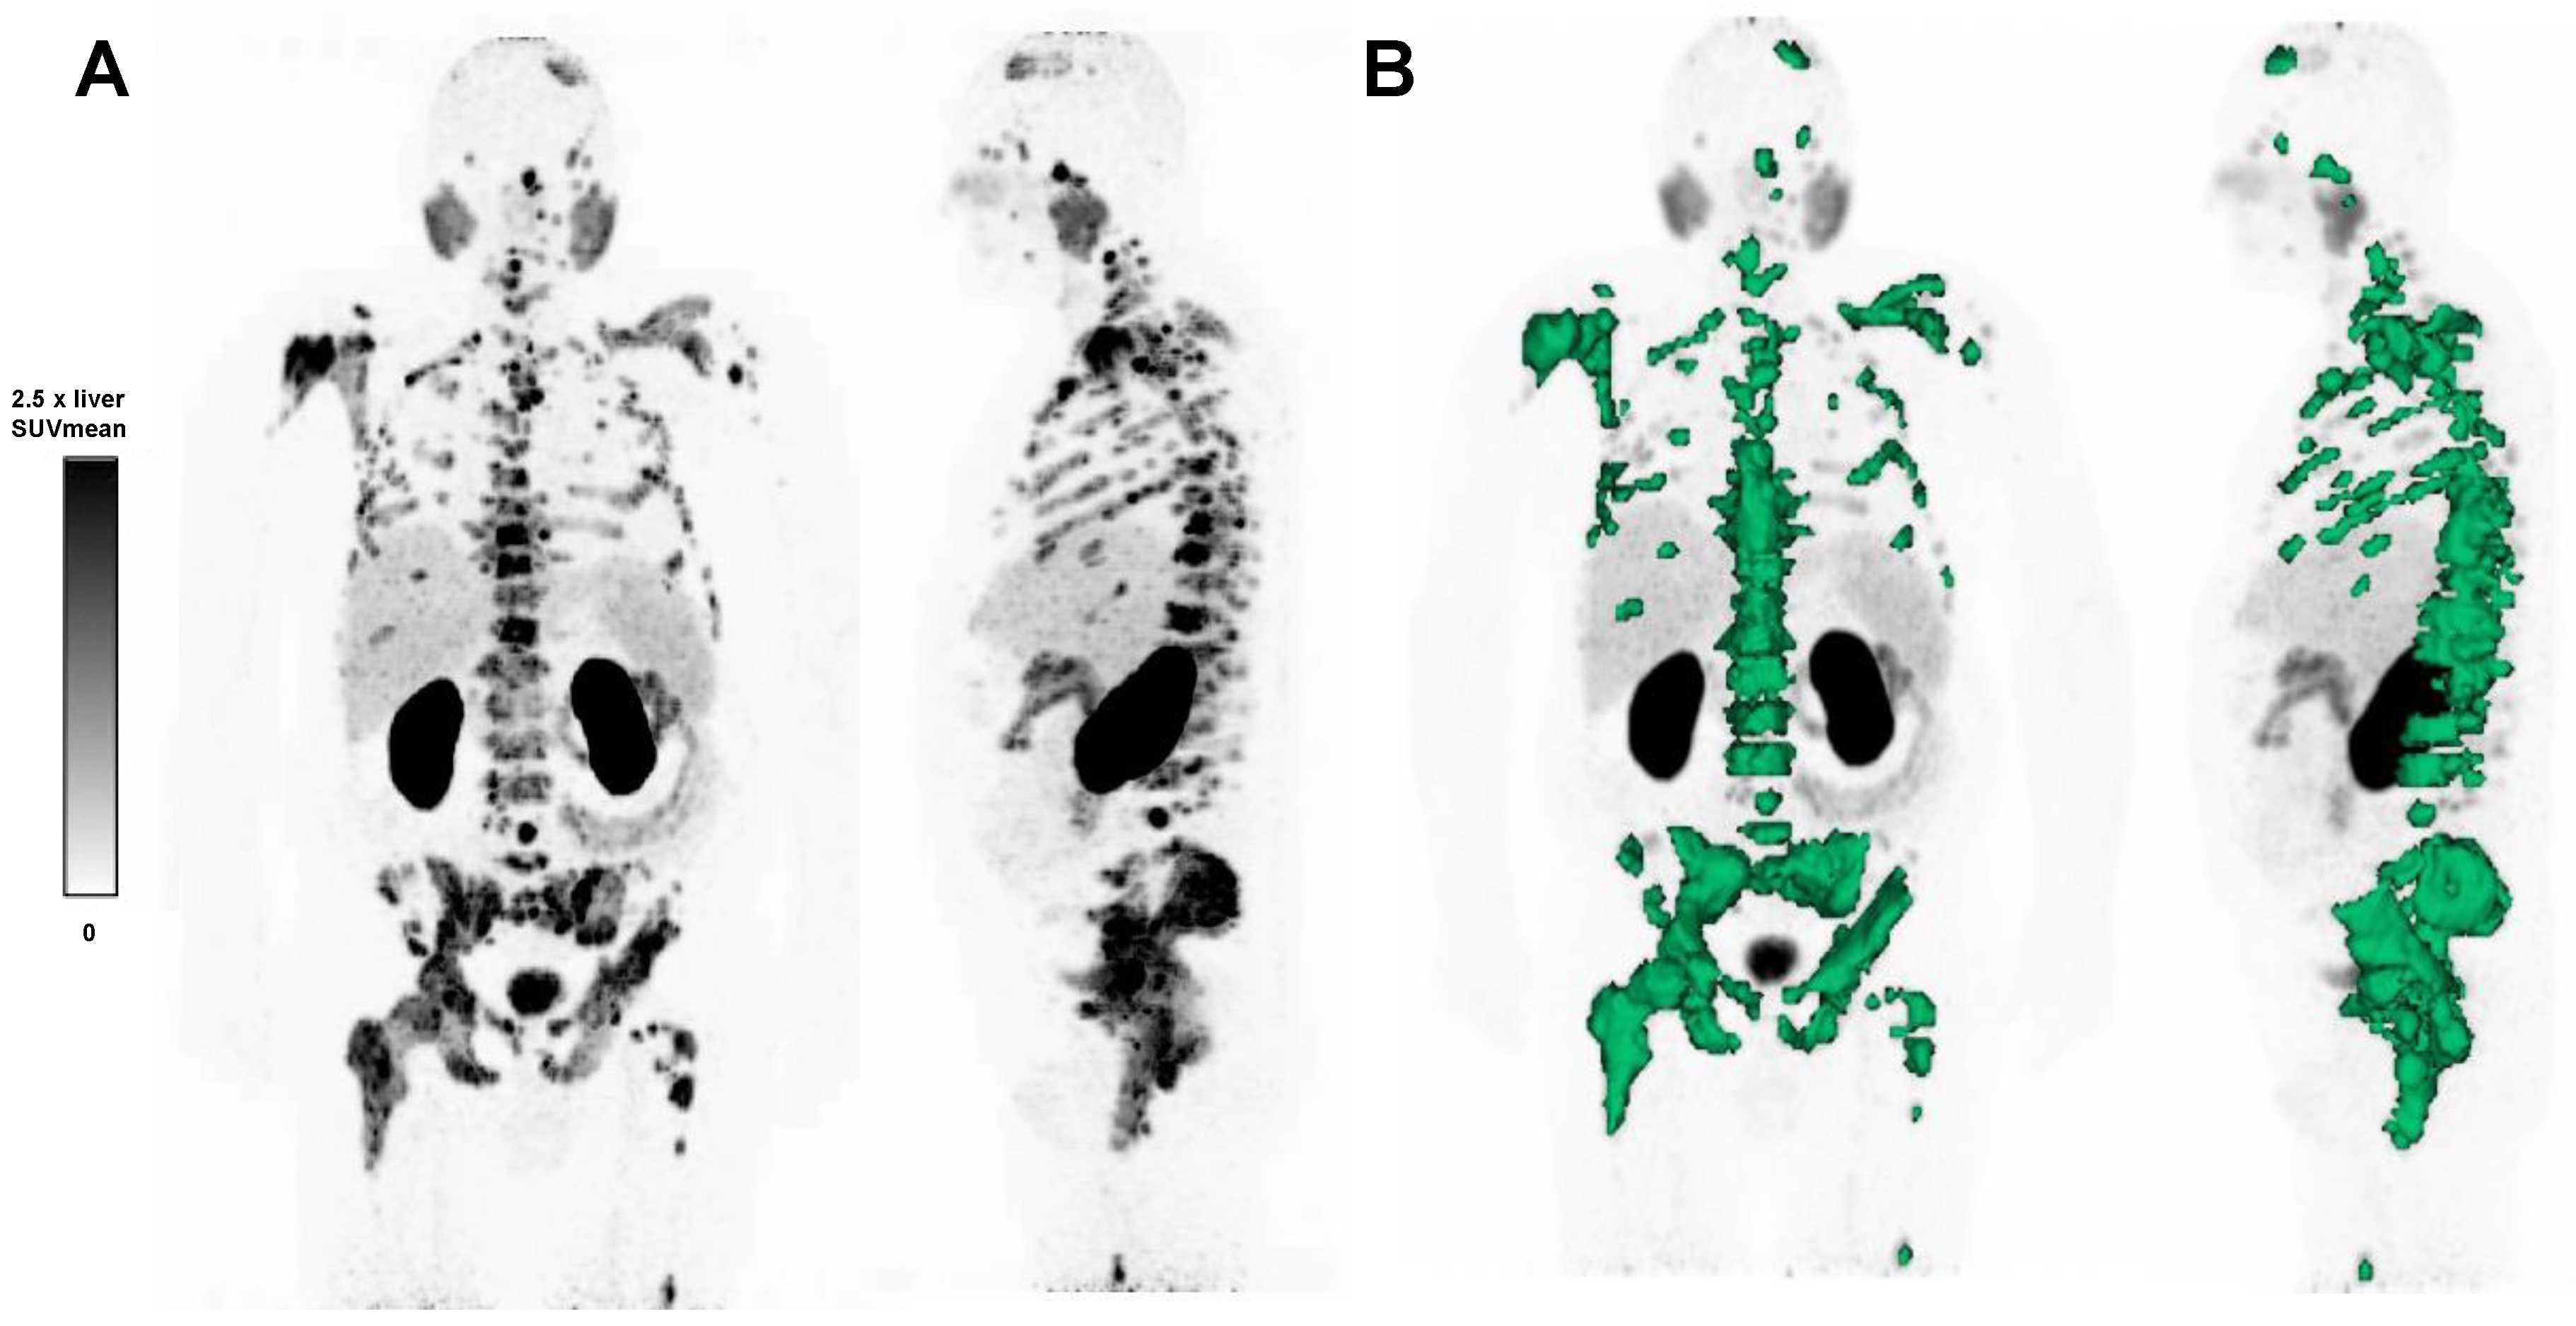

2.4. Calculation of TLP

2.5. 177Lu-PSMA-617 RLT